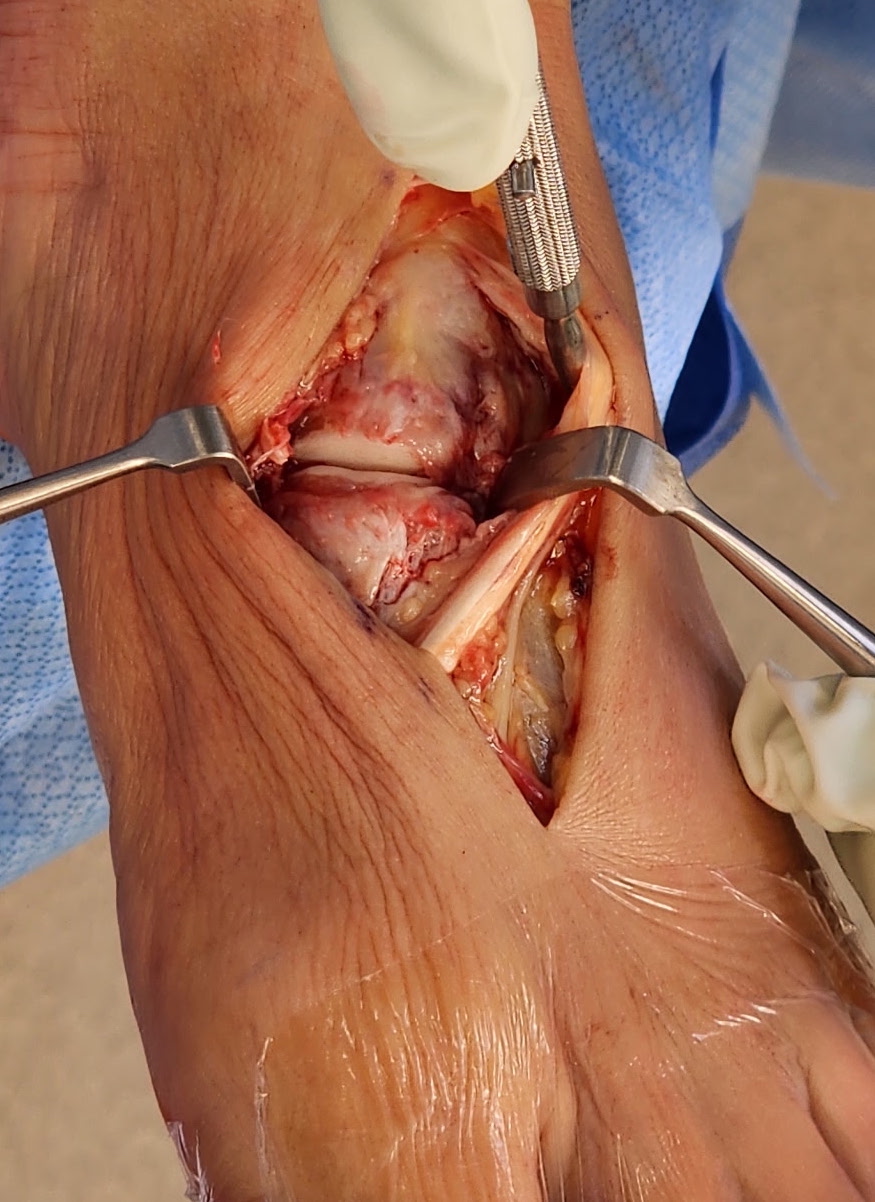

Approach and reduction

Reduction

- medial incision over medial cuneiform

- clamp medial cuneiform to base 2nd metatarsal